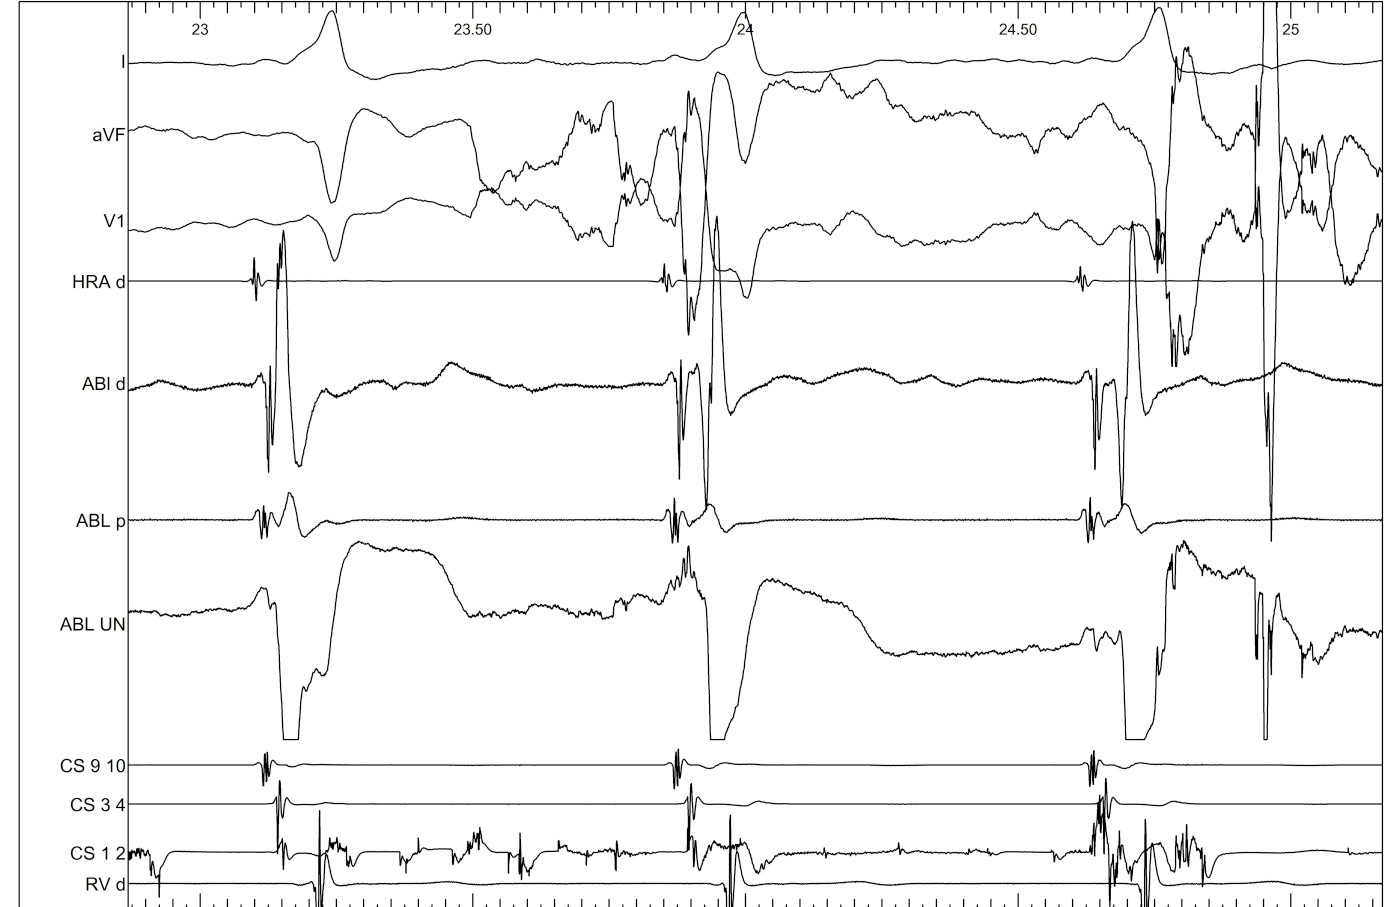

Mapping during AF

palani_006.jpg

Ablation during AF

palani_004.jpg